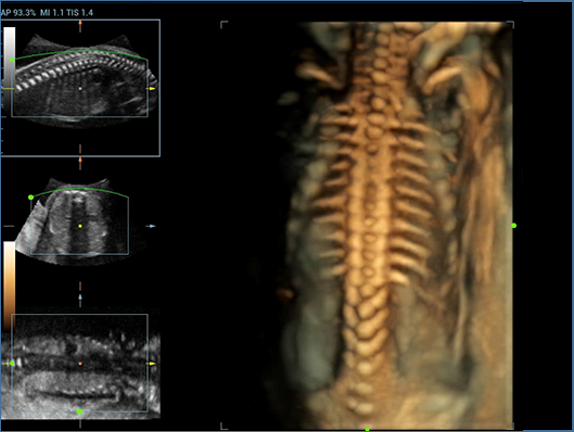

Resona 7, ĂŒstĂŒn dĂŒzeyde g?rĂŒntĂŒ kalitesine ek olarak, vaskĂŒler hemodinamik de?erlendirmesi i?in devrim niteli?indeki V Ak??? ile fetĂŒs CNS tan?lamas? i?in 3 boyutlu veri kĂŒmesinden dĂŒzlem g?rĂŒntĂŒsĂŒ alma konusunda en iyi birime sahip oldu?undan, klinik ara?t?rma yeterliklerini de art?rmaktad?r. En sezgisel, harekete dayal? ?oklu dokunmatik i?letim ile tĂŒm temel klinik ?zellikleri bir araya getiren Resona 7, ultrason yenili?i konusunda ger?ek anlamda yeni dalgalara ?ncĂŒlĂŒk ediyor.